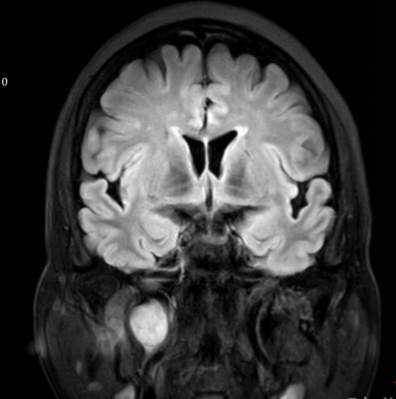

(2023-05-15 10:00,本院)行磁共振(颅脑)检查提示:右侧乳突区异常信号,考虑恶性、软骨来源肿瘤,软骨肉瘤可能性大。(集体讨论意见);脑内散在多发缺血灶。

(2023-05-12 10:15,本院)行CT(颅脑)检查提示:右侧颞骨广泛骨质破坏,伴巨大软组织肿块,性质待定,考虑肿瘤性病变,颈静脉球瘤?软骨源性肿瘤?请结合临床及病理进一步明确。